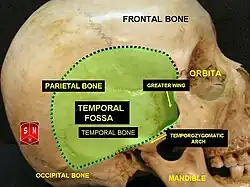

Cavidade temporal.

Cavidade temporal. -